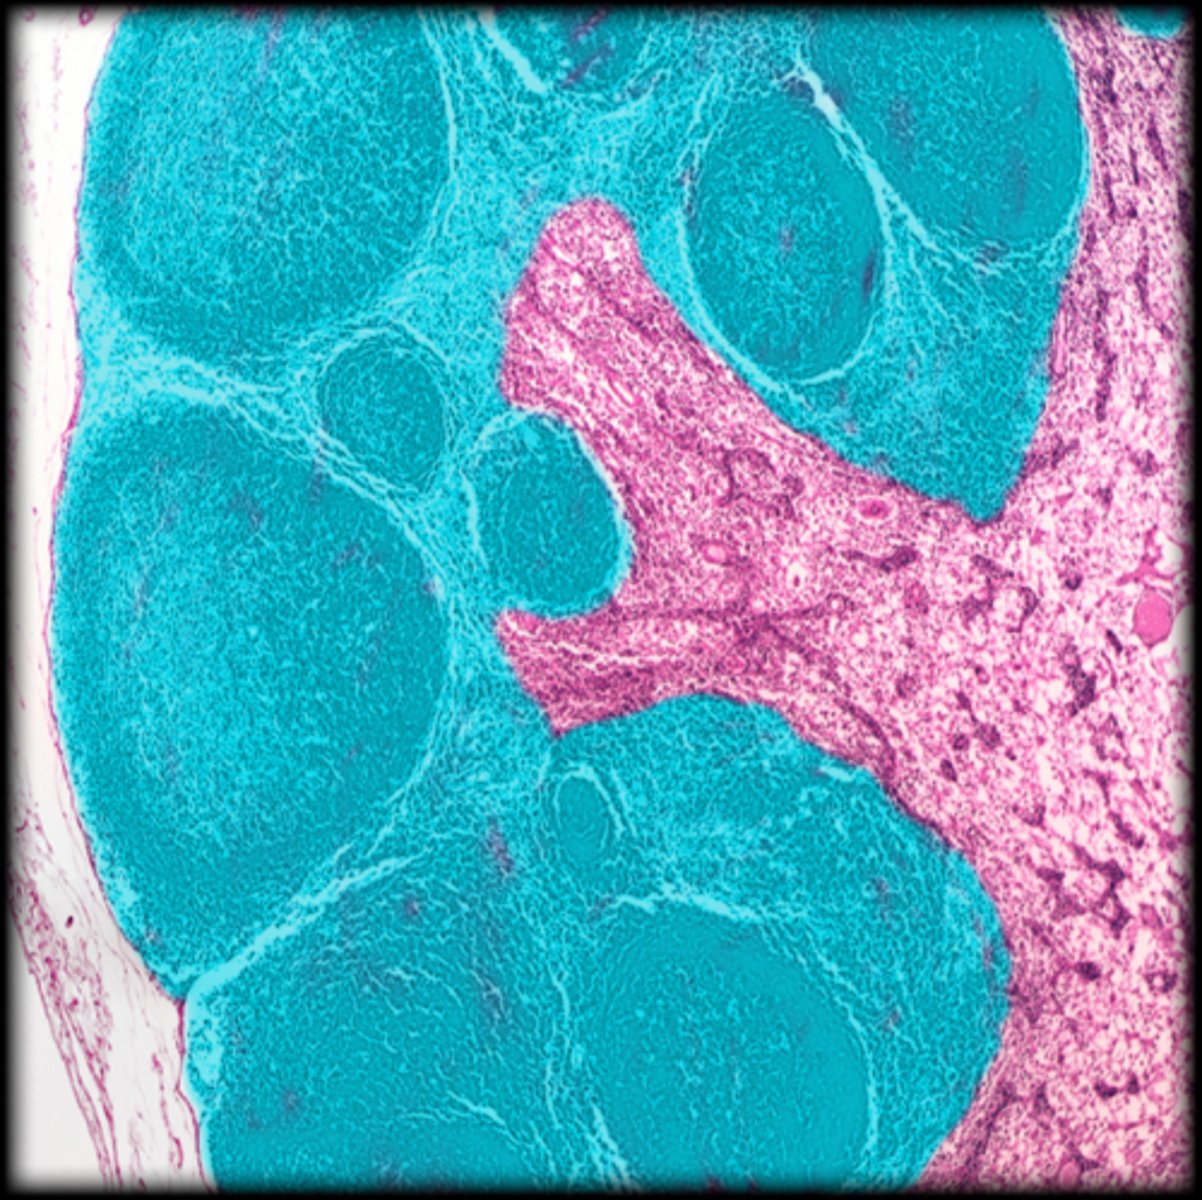

Spleen

central white pulp

red pulp

white pulp